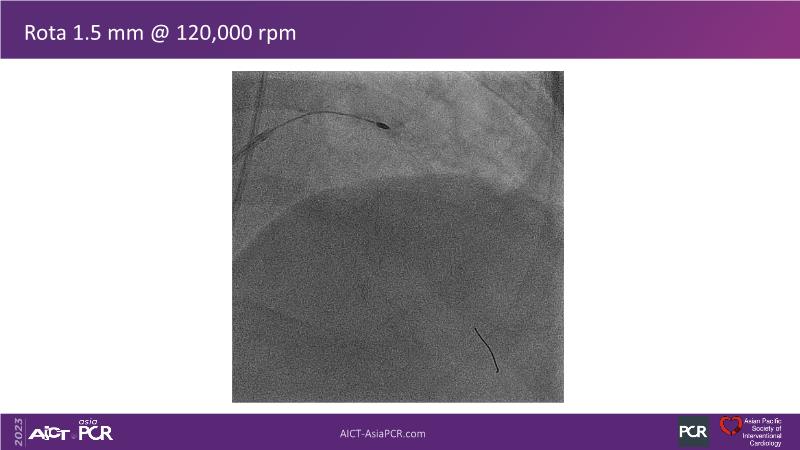

This session is recommended for you if you are seeking insights into the advantages of using IVUS imaging over visual assessment for better outcomes in left main bifurcation procedures. Discuss with experts the benefits of using RotaCUT in lesion preparation for left main bifurcation and explore the impact of high radial strength stents on the procedure's success.

• To see advantages of RotaCUT as part of lesion preparation in left main bifurcation